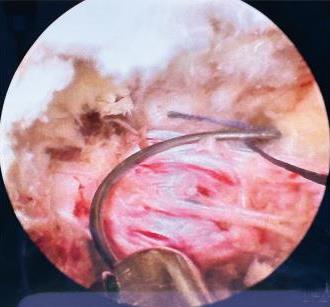

• 获得性免疫缺陷综合征合并马尔尼菲篮状菌导致肠道感染的内镜下表现(附6例报告)

2026, 32(3):84-88. DOI: 10.12235/E20250461

摘要 (32) HTML (27) PDF 3.50 M (26) 评论 (0) 收藏

摘要:目的 探讨获得性免疫缺陷综合征(AIDS)合并马尔尼菲篮状菌(TM)感染导致肠道感染的内镜下特征。方法 回顾性分析2022年11月-2024年10月于该院确诊为AIDS合并TM感染导致肠道感染的6例患者的临床资料。包括:临床症状、实验室检查、影像学检查、内镜检查和病理检查等。结果 6例患者中,男5例,女1例;发病年龄26~67岁;AIDS合并TM感染导致肠道感染患者的临床表现为:腹泻、腹痛、腹胀和恶心呕吐。其中,2例有消化道出血表现。实验室检查:6例患者外周血白细胞计数为(1.37~4.49)×109/L,血红蛋白计数为(67~99)g/L;CD4+T淋巴细胞为(1~52)个/μL,CD8+ T淋巴细胞为(61~321)个/μL,CD4+T淋巴细胞/CD8+T淋巴细胞比值为(0.01~0.18)。6例患者均行HIV RNA检测。其中,5例HIV RNA阳性。血培养:可见丝状真菌,报告显示为TM。影像学检查:6例患者CT结果可见肠系膜及腹膜后多发淋巴结肿大。内镜检查:6例患者内镜下均可见肠道病变。其中,十二指肠糜烂溃疡2例,结肠多发糜烂溃疡4例。病理检查:6例患者幽门螺杆菌(Hp)结果均为阴性,黏膜下可见成簇的小球形真菌孢子,符合TM感染;特殊染色:PAS(+),六胺银染色(+)。结论 当AIDS晚期患者出现消化道症状时,应警惕TM感染,病变部位常见于全结肠和直肠,亦可累及十二指肠,内镜下表现多为溃疡、糜烂和隆起性病变,形态表现无特异性;及时行胃肠镜检查、病理活检、特殊染色和免疫组化是确诊的关键。